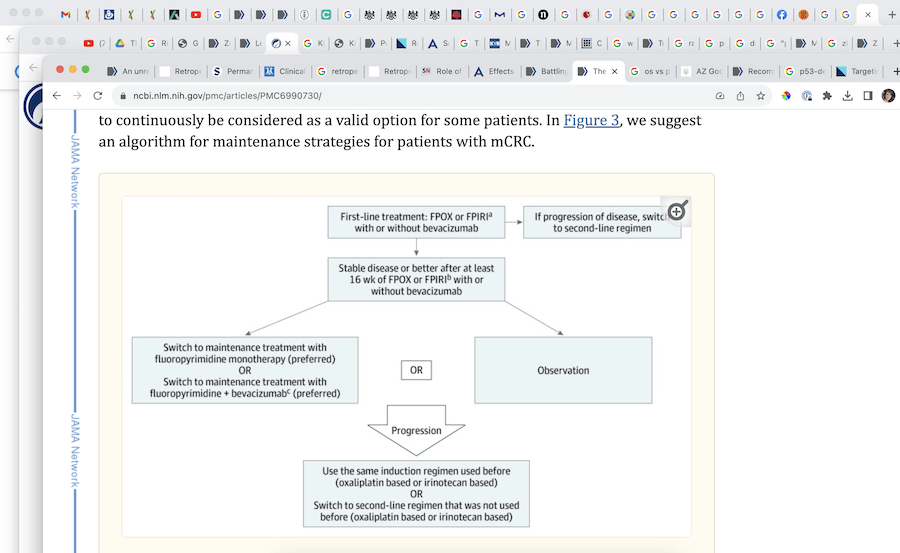

NIH PMC6990730

"After surgery, regarding low dose maintenance chemo vs observation, the studies show that for my case, the chemo delayed PFS (time to disease progression), but had no effect on OS (5-year survival). My concern is about developing a resistance if I stay on the drug. If we do intermittent (observation) instead, and it returns, wouldn't it be more likely to respond if we bring back what we knew worked the first time?" He said we'd likely go to something stronger either way, but added, "That's a good question, I would prefer to do some sort of maintenance plan, but if your next scan and the operative findings are very encouraging, we could consider stopping and watching you."

Through my research, I’d come across studies showing that, in certain cases like mine, a period of observation (no chemo) could be a scientifically valid option—as long as the next scan and the surgical findings looked good.

"When compared with observation, maintenance therapy conferred a PFS benefit (HR = 0.58; 95% CI, 0.43-0.77) but no OS benefit (HR = 0.91; 95% CI, 0.83-1.01)."

"Although a maintenance strategy with a fluoropyrimidine with or without bevacizumab is preferred over continuous induction therapy for metastatic colorectal cancer, shared decision-making should include observation as an acceptable option, given the lack of significant overall survival benefits."

"It is generally accepted … that patients with complete clinical responses may discontinue chemotherapy until radiographic evidence of disease recurrence emerges. Although the overwhelming evidence supports the use of chemotherapy in metastatic CRC, a subpopulation with indolent disease probably exists, where observation may not be unreasonable."